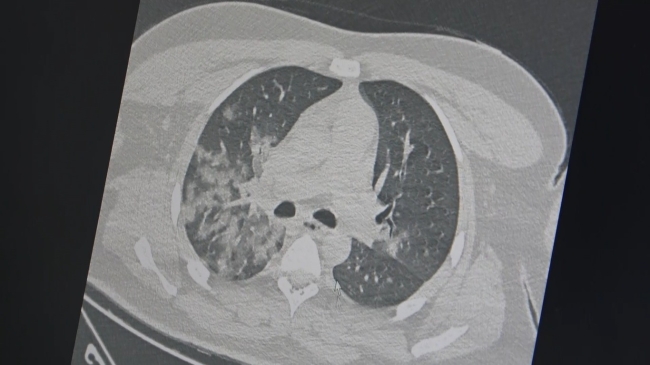

Özkaya, kovid-19 salgını sonrası acil servislerdeki genç hastalarda ani ölümle sonuçlanan akciğer ve kalp-damar hastalıklarında ciddi bir artış gözlemlendiğini ifade etti. Ayrıca, bu artışın kaynağının kovid-19 aşıları değil, virüsün damar hasarına yol açması olduğunu vurguladı. İngiltere’de 46 milyon kişi üzerinde yapılan araştırmaya atıfta bulunan Özkaya, kovid-19 aşılarının damar tıkanıklığı sonucu kalp krizi ve inme riskini azalttığını belirtti.

Prof. Dr. Özkaya, damar iç duvarında (endotel) hasarın, vücudun hareketsiz kalması, genetik yatkınlık veya ilaç kullanımı (doğum kontrol hapları gibi) ile pıhtılaşma riski oluşturduğunu söyledi. Kovid-19 virüsünün enfekte ettiği kişilerin kan plazmasında meydana gelen "sitokin fırtınası" ve toksik etkilerin damar iç duvarında ciddi hasara yol açarak, pıhtı oluşumunun ilk aşamasını başlattığını ifade etti. Bu durumun, kalp, beyin ve akciğer damarlarında ölümcül sonuçlarla karşılaşılmasına neden olduğunu açıkladı.

Aşıların, virüs yükünü azaltarak hem hastalığın şiddetini hem de damar iç duvarındaki tahrip edici etkisini azalttığını belirten Özkaya, “Aşılar, kovid-19’un damar tıkanıklığına yol açan etkilerini azaltarak, akciğer, kalp ve beyin damarlarında ölümcül tıkanıklıkları da azaltıyor” dedi.